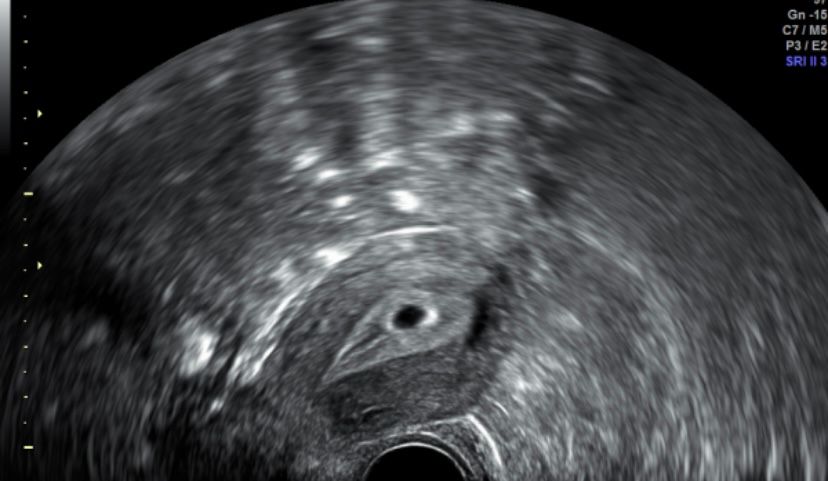

Первое УЗИ

Сегодня ровно 5 акушерских недель, сходила на УЗИ, т.к. очень сильно тянул бок справа, отдавало в ногу и в поясницу справа. Беременность подтвердили маточную 🤗 Теперь я спокойна. Сегодня сказала мужу и старшему сыну, оба прослезились. Теперь можно выдохнуть. 😊 И наше первое фото